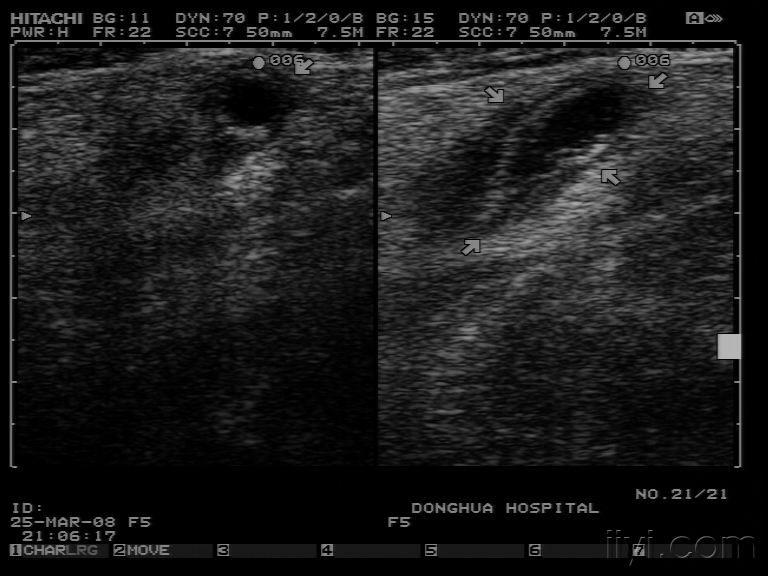

【分享】经典病例-----化脓性阑尾炎穿孔伴腔内粪石超声图片及术后

第二例急性化脓性阑尾炎

急性化脓性阑尾炎数例

急性化脓性阑尾炎

化脓性阑尾炎

急性化脓性阑尾炎图片

急性阑尾炎b超图片